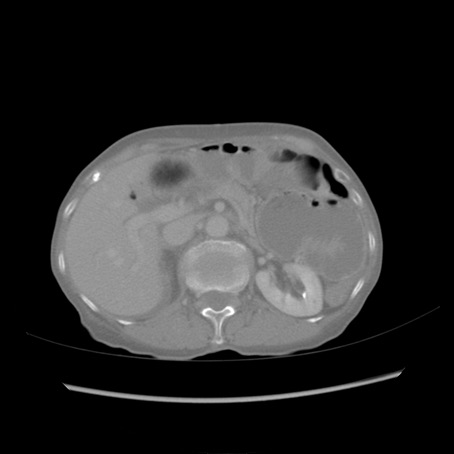

冠状断像

症例25(横断像)

【症例】80歳代女性

【主訴】胸のつかえ感

【現病歴】約9時間前に食後から胸のつかえた感じあり、嘔吐あり、来院。

【既往歴】胃癌(全摘)、胆摘、虫垂炎

【身体所見】心窩部に圧痛あり、反跳痛なし。

【データ】WBC 5700、CRP 0.05